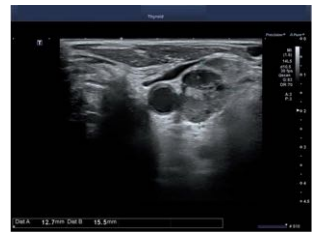

Um paciente de 62 anos foi submetido a tireoidectomia total por carcinoma papilífero de tireoide há 10 anos. Em seguimento houve elevação da tireoglobulina sérica e foi solicitado ultrassom cervical, por meio do qual se obteve a imagem abaixo.

É correto afirmar, a partir dessa imagem, que se trata de um linfonodo: